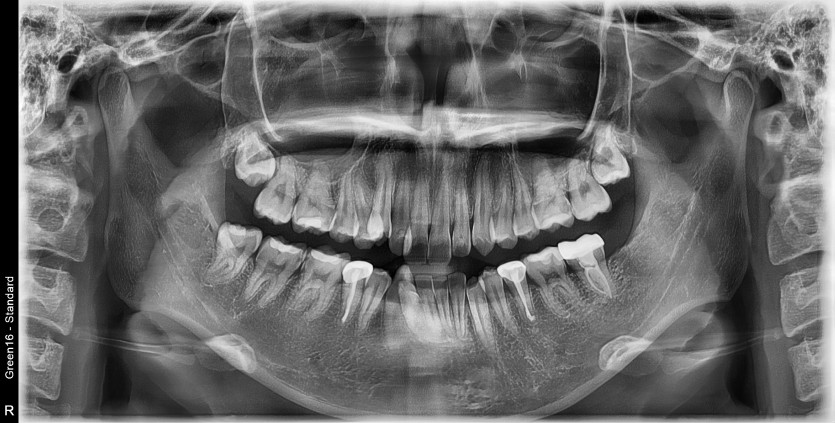

#18,48 사랑니 발치

구강 외과 전문의가 당일 발치했습니다.